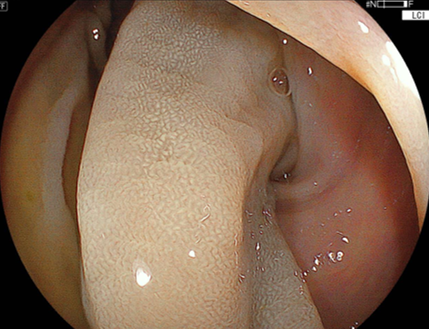

切除後の潰瘍底(かいようてい):術直後の出血なく切除

されました。

切除後の潰瘍底に後出血予防のクリップを追加しました。

この症例は、術中出血および後出血を認めませんでした。